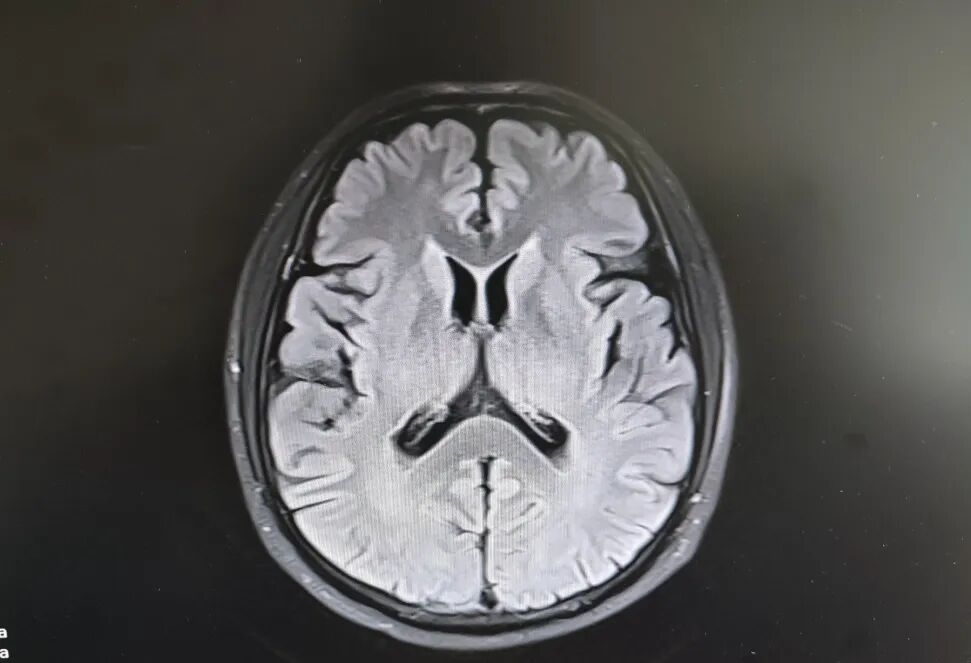

患者头部磁共振影像

就在看似陷入僵局时,关键的血液检查结果出来了——RPR阳性!这个结果像一盏明灯,指明了方向。原来,导致大爷眼病的幕后黑手,竟是由苍白密螺旋体(引起梅毒的病原体)感染引起的神经损害。经过针对性治疗,十几天后,大爷的病情逐渐好转,眼皮能抬起来了,重影消失了,眼球转动也灵活了!